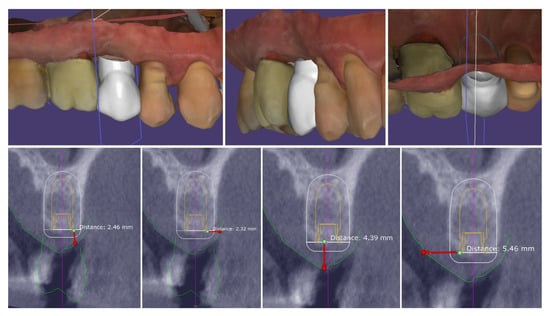

Digital planning of the dental implant was performed. It was determined that there was sufficient crestal bone volume to place the implant in the most appropriate prosthetically oriented position, for which a surgical guide was prepared for fully guided implantation (Figure 5).

Figure 5.

Digital planning of the dental implant.

The performed measurements showed adequate soft tissue dimension (≥3.5 mm) for stable peri-implant tissues crestally, 4.3 mm, and palatally, 5.4 mm, but at the buccal site, a pronounced volume deficiency was detected (2.3 mm soft tissue thickness), for which a soft tissue augmentation procedure was planned (Figure 6).

Figure 6.

Soft tissue dimensions analysis.